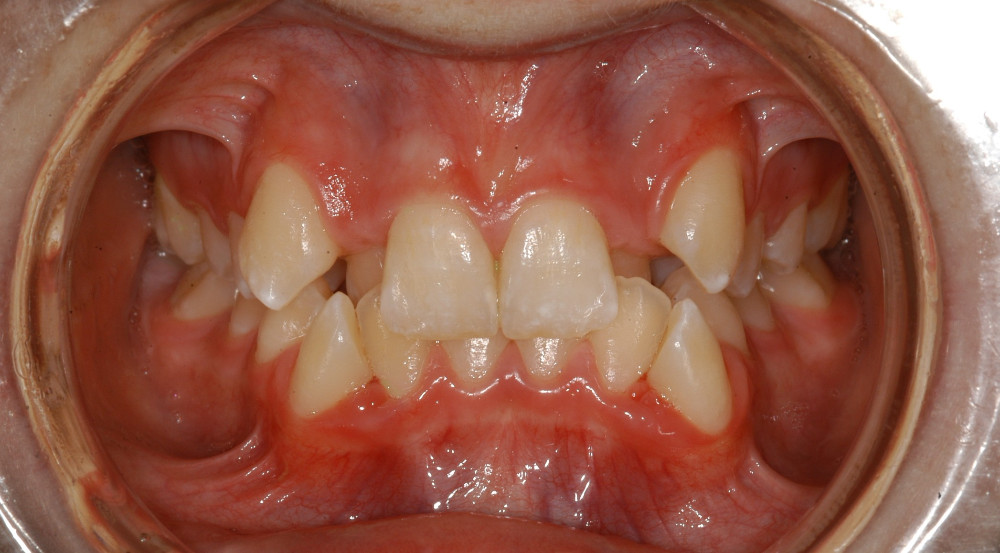

| Sehr schwere Kiefer-und Zahnfehlstellung Dauer ca. 2-3 Jahre, ev. mit Kieferchirurgie | Metalbrackets | ja | ja | Bild |

| ev. mit Chirurgie in Bern (Lindenhofspital) | Bild |